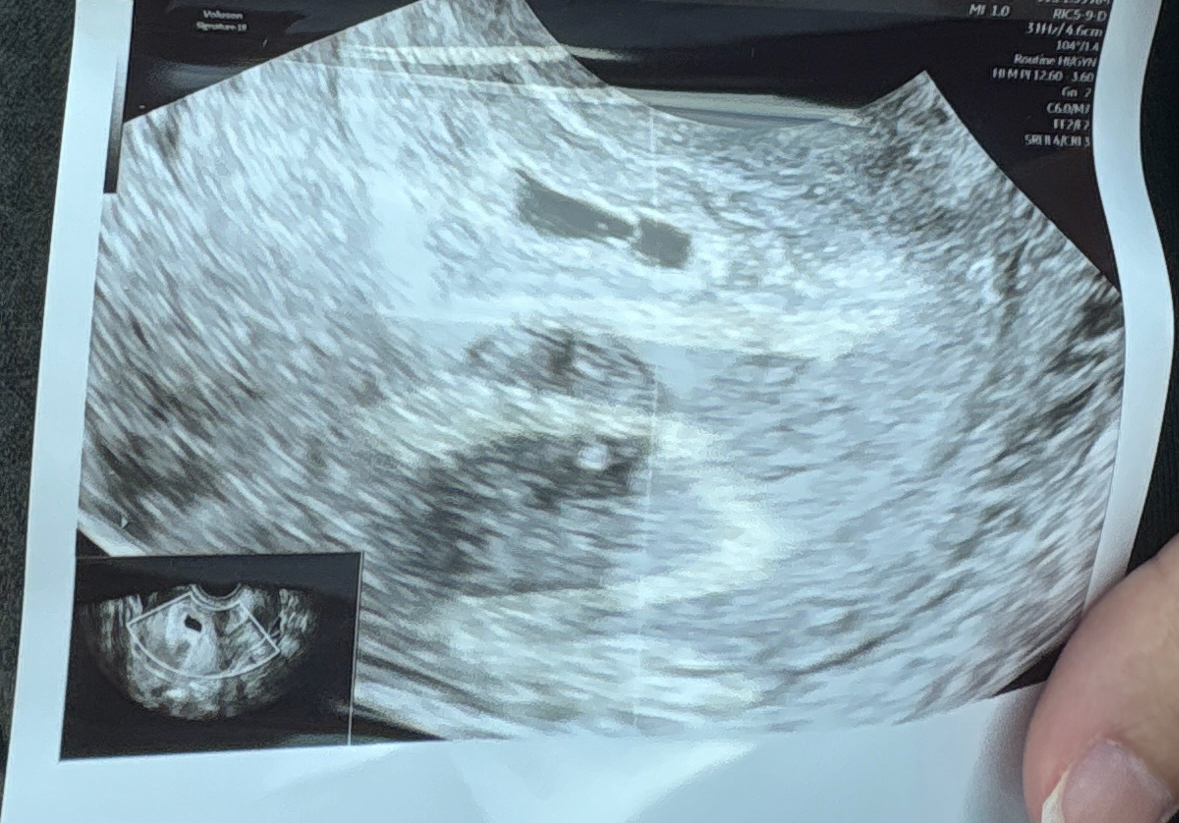

تاكد ازا الحمل توام ام لا

انا حامل عملت سونار طلع في كيسين للحمل الكيس الاول عمره خمس اسابيع والكيس الثاني عمره اربعه اسابيع ممكن يكون...